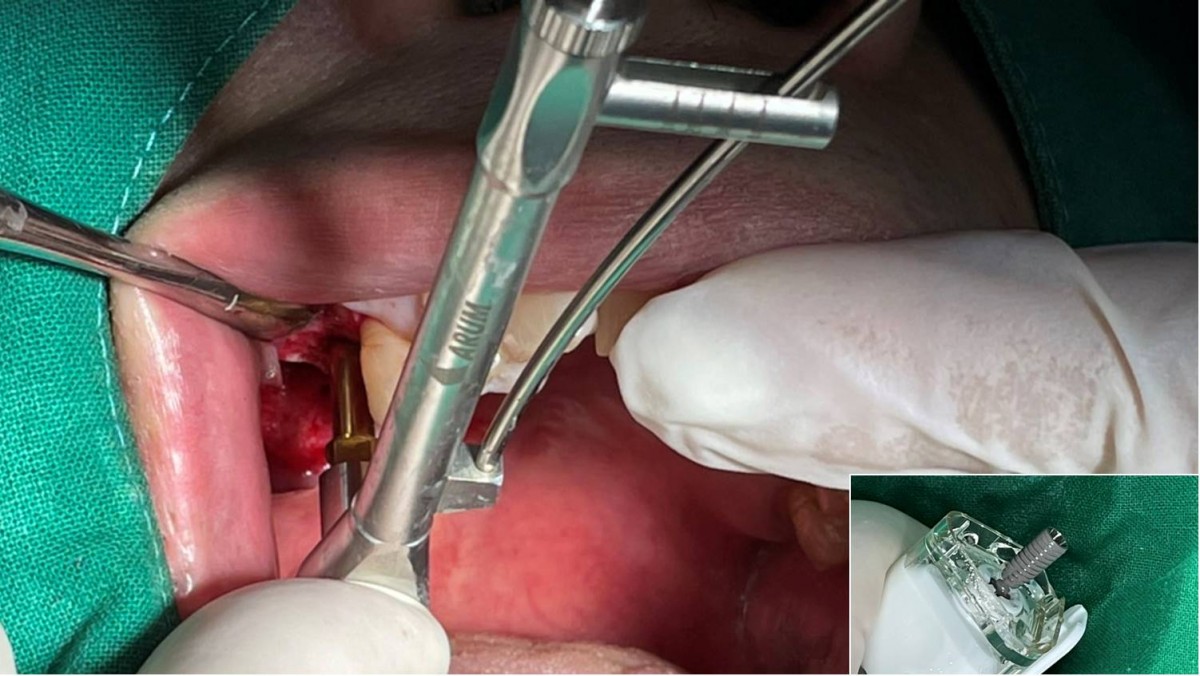

Maxillary Sinus Graft, 2 Implants, Crown Contouring

<GCaks> A 56-year-old male patient had pain-inducing caries, and perio-involved tooth mobility resulted in a tooth fracture at 1st molar. And it was removed months ago. He was a heavy smoker and showed poor oral hygiene.